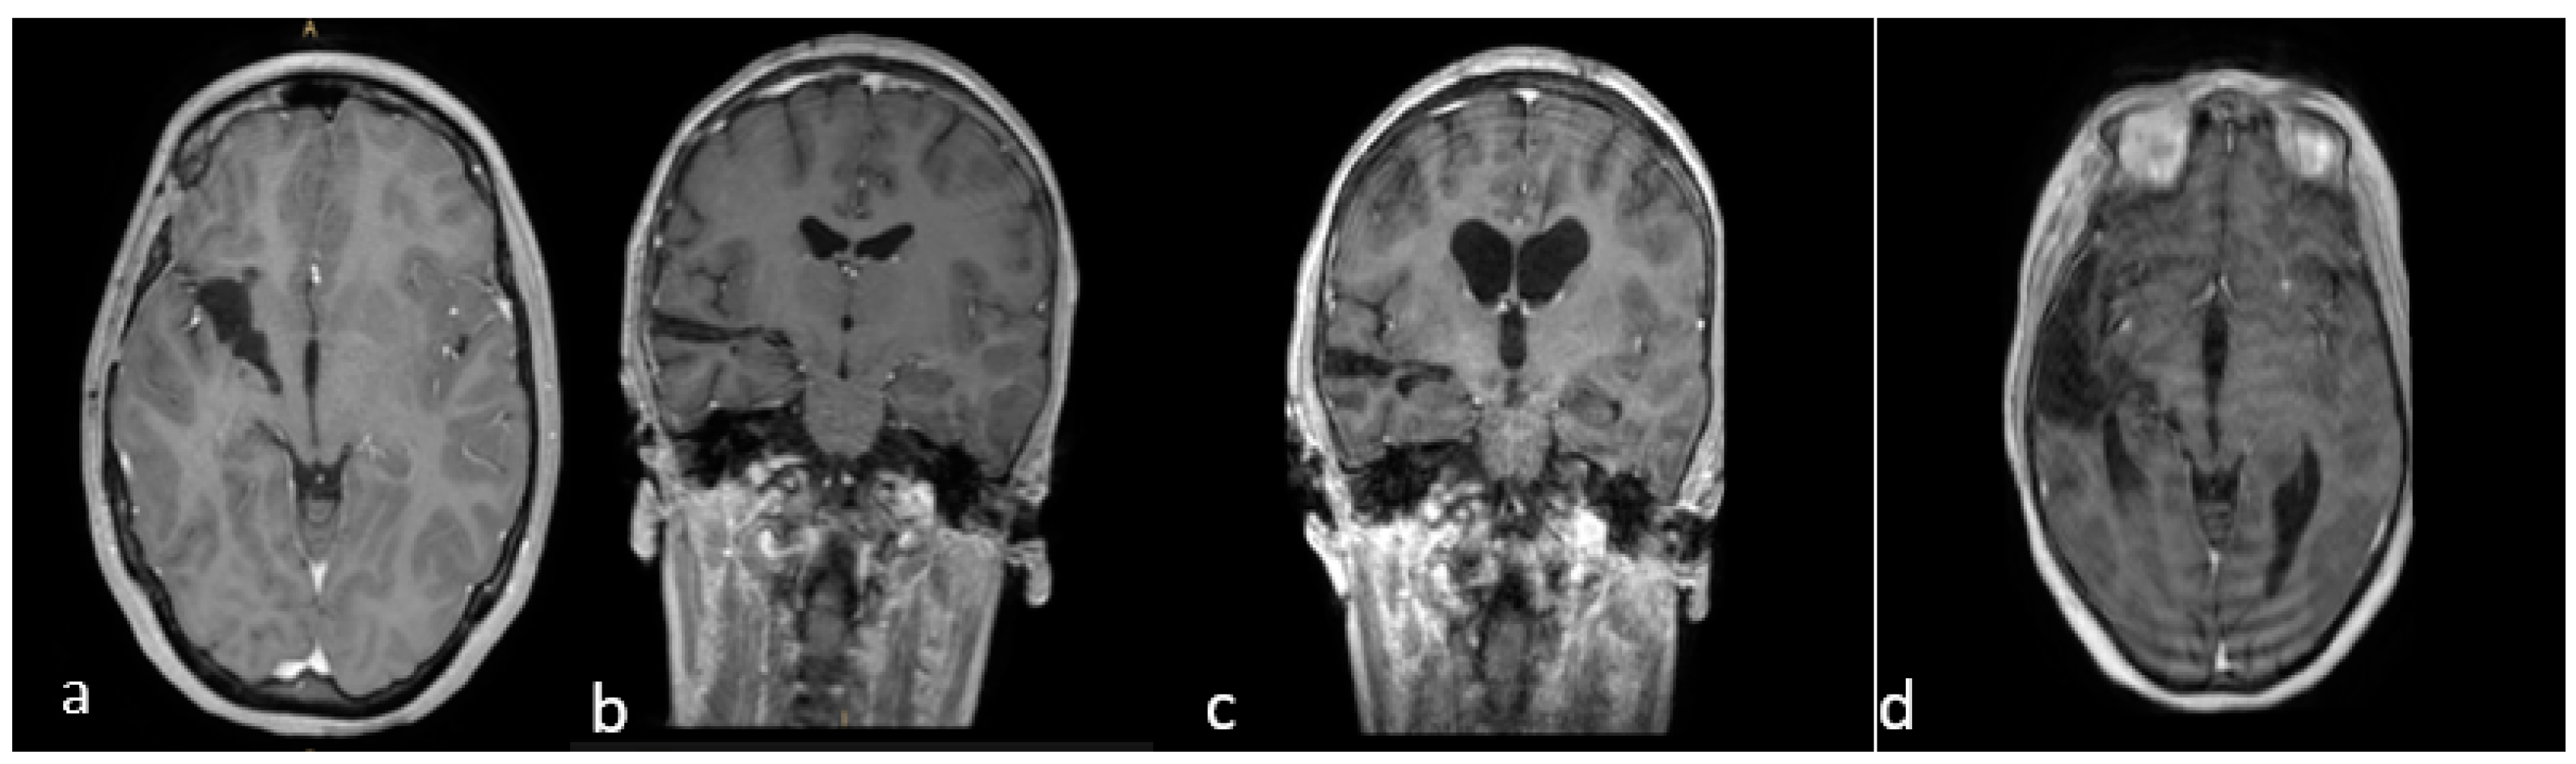

Even a subtotal resection offers a good long-term outcome, as shown in our series. Five cases with subtotal resection were clinically and radiologically stable at long-term follow-up (Figure 5).

(a–d) Brain MRI, T1-weighted with gadolinium. Last follow-up of Case A (a,b) and Case B (c,d). (a,b) Brain MRI, T1-weighted with gadolinium, in the axial and coronal planes of Case A, showing good control of the disease (2021). (b–d): MRI, T1-weighted with gadolinium, in the coronal and axial planes of Case B, showing no evidence of relapse five years post-op.